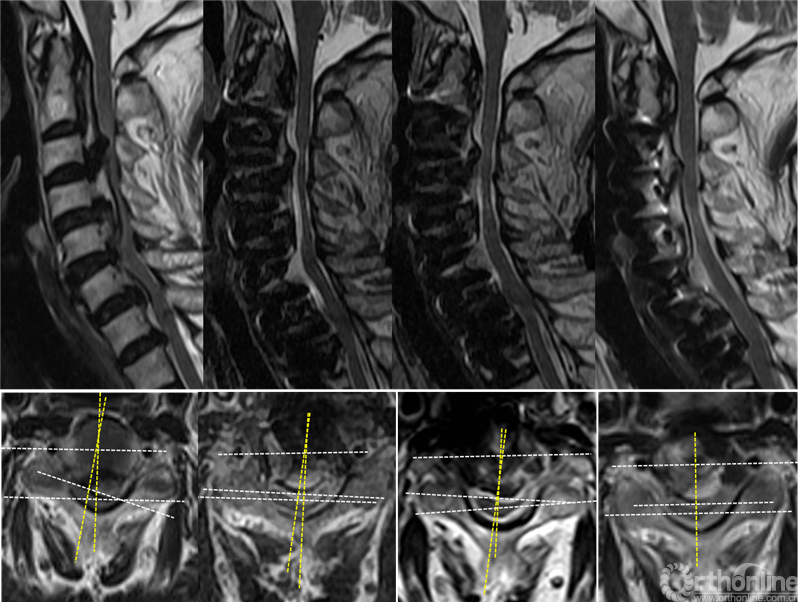

典型病例:刘某,女性,69岁,因“四肢麻木、疼痛,伴行走不稳、排尿无力1年,加重1月”,保守治疗无效。术前MRI显示C2 – C7脊髓明显受压,脊髓曲度变直,脑脊液带消失,C2-C7后纵韧带骨化,术前脊髓旋转和偏移角分别为36.3°和14.2°术前JOA评分为9。

在海军军医大学附属长征医院行ACAF治疗(手术节段C2-C7),脊髓减压彻底,脊髓旋转和偏移角显著变小。末次随访时,脑脊液、脊髓面积恢复良好,脊髓旋转和偏移几乎接近0°,由于脊髓横截面面积和位置恢复,脊髓中心前移1mm,恢复原位,JOA评分提高到15分,改善率为75%。脊髓减压彻底,神经功能改善优异,且未发生颈5神经根麻痹。

患者男性,46岁,主诉“双上肢麻木、无力、疼痛5年,加重1月”术前MRI显示C5-C7脊髓受压,骨化物压迫平面的脊髓旋转和偏移角分别为39.6°和17.4°。

在海军军医大学附属长征医院行C3-C7节段椎管成形术,脊髓间接减压但不完全,脊髓旋转和偏移角分别变为23.5°和13.6°,且术后出现右上肢不能上抬(C5神经根麻痹),原因可能是C4/5水平的右侧神经根由于偏右侧型骨化物压迫受到牵拉,加上脊髓向后漂移,麻痹侧神经根可能受到更大的张力。末次随访时,脑脊液、脊髓面积仍恢复较差,脊髓旋转和偏移角仍较大,脊髓向后漂移3.0mm,JOA评分由术前9改善到12,改善率为37.5%,仍残留部分麻木疼痛症状。